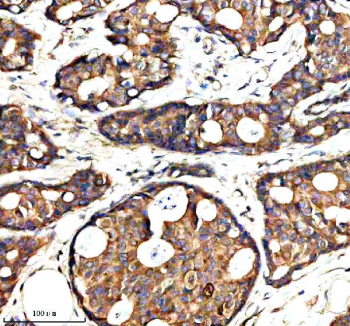

Immunohistochemical staining of SYAP1 using anti-SYAP1 antibody. SYAP1 was detected in a paraffin-embedded section of human breast cancer tissue. Heat mediated antigen retrieval was performed in EDTA buffer (pH 8.0, epitope retrieval solution). The tissue section was blocked with 10% goat serum. The tissue section was then incubated with 2 ug/ml rabbit anti-SYAP1 antibody overnight at 4oC. Peroxidase Conjugated Goat Anti-rabbit IgG was used as secondary antibody and incubated for 30 minutes at 37oC. The tissue section was developed using an HRP secondary and DAB substrate.